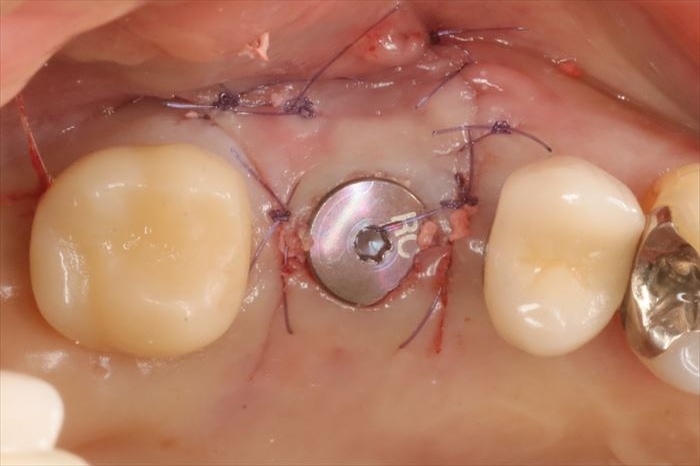

吸収性の縫合糸で縫合して本日の撤去・埋入オペは終了です。

インプラントの埋入位置の修正も出来て安堵します。